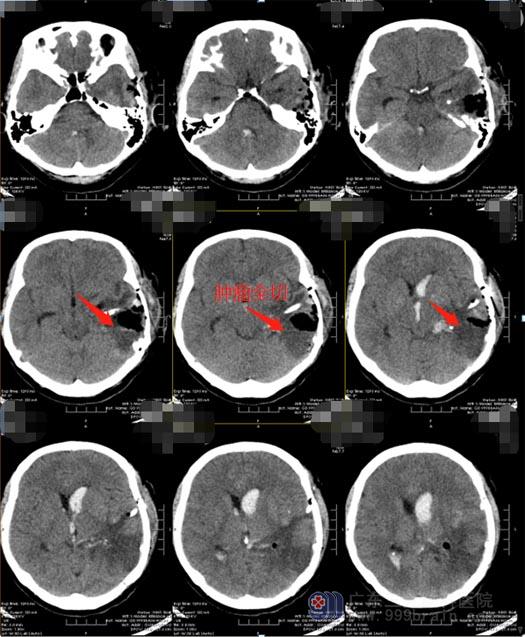

医院副院长、神经外五科主任鲁明带领团队对病例进行了详细的讨论:此脑膜瘤血液供应极为丰富,手术治疗出血量大,对术野影响也较大,甚至会因为止血难度大而无法对肿瘤进行完全切除、肿瘤切除后的瘤腔出现不同程度的并发症。最终选择了对患者脑部损伤最小的治疗方案:先行DSA栓塞,由于介入和栓塞治疗的不断发展,手术前根据血管造影结果了解血液供应情况,并进行血管栓塞,可以保证手术治疗的安全性;肿瘤周围主要的血管栓塞后,能大大降低手术中出血的可能,还可以将肿瘤最大范围地切除,更好的保护正常脑组织。

家属也非常赞同该手术方案。12月29日,杨女士先行DSA栓塞,术中可以清晰地看到左侧脑室内异常的染色,呈类圆形,考虑肿瘤占位病变,大小约4cm×4.5cm×4cm,主要由左侧脉络膜后内、左侧脉络膜前动脉末端分支参与供血,将左侧脉络膜后内动脉远端分支血管栓塞,效果明显,肿瘤供血消失,因左侧脉络膜前动脉末端分支血管比较细,微导管到位困难,没有进行栓塞。随后送杨女士至手术室在全麻下行“左侧脑室内占位性病变切除术”。全部手术过程非常的顺利。术后杨女士即清醒,四肢活动无异常。